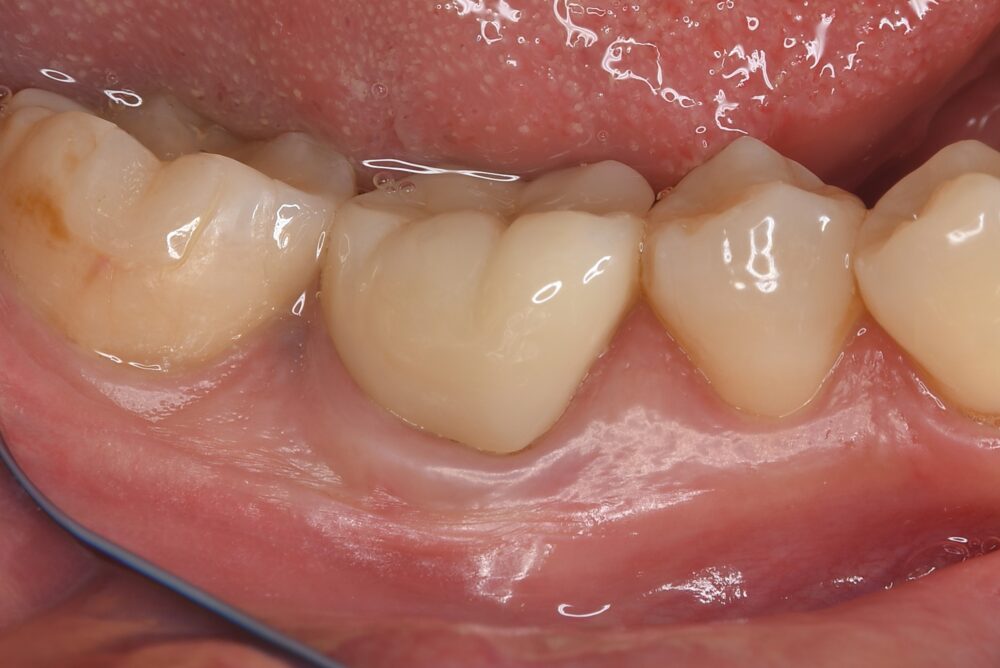

症例1:パーフォレーションリペア症例

(歯の中に大きな穴が空いてしまっているのを埋めて再生を促す治療)

AFTER |

人為的根穿孔を起こした部分に感染を起こしており、歯周ポケットが9㎜ありました。 ラバーダム防湿とマイクロスコープを使用して丁寧に治療を行いました。 殺菌性があり歯を補強することのできるMTAという根管充填材料を使用して、歯周ポケットは2㎜に改善しました。 |